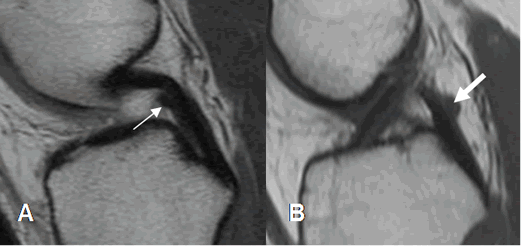

Para una adecuada valoración del LCA, se deben orientar los cortes sagitales con una rotación externa entre 20º y 25º de la rodilla.

El ligamento se aprecia como una estructura hipointensa en todas las secuencias, pudiendo reconocer sus 2 bandas. Pueden encontrarse áreas hiperintensas en su parte distal, por interposición de grasa o sinovial entre las fibras o degeneración mucoide. (2). (Fig 13 y 14).

La orientación del LCA es uno de los signos con mayor sensibilidad y especificidad, de lesión ligamentaria.

Fig 13. LCA normal.

A: RM sagital en T1, B: RM sagital en T2 y C: RM sagital en FFE. Ligamento normal,

hipointenso en todas las secuencias.

Fig 14. LCA normal.

RM coronal en T1. Bandas normales del LCA. Anteromedial (Flecha delgada) y posterolateral (Flecha gruesa).

Fig 15. LCA normal.

A: RM sagital en T1. Relación normal, con el platillo tibial.

B: RM sagital en T2. Ruptura del LCA, el cual está horizontalizado y con disminución del ángulo.

Fig 16. LCA normal.

A: RM sagital en T1. Angulo normal de vértice superior, con la línea intercondilea.

B: RM sagital en T2. Ruptura del LCA, con ángulo de vértice inferior.